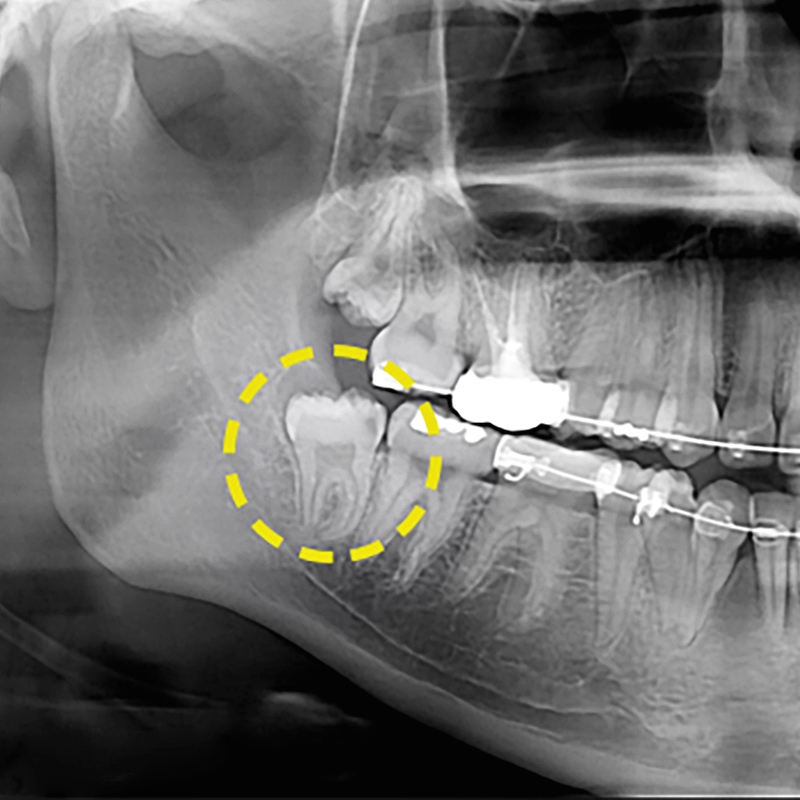

환자분의 엑스레이를 확인해본 결과 사랑니 자체가 다 자랐지만 잇몸에 매복되어 구강내에서 직접 눈으로 볼 때는 잘 보이지 않고 앞부분만 살짝 보이기 때문에 이제 사랑니가 나는 것인가? 하는 생각을 하실 수 있겠는데요. 엑스레이를 찍어본 결과 잇몸안에서 사랑니가 이미 다 난 상태이며 어금니쪽의 머리 부분과 뿌리부분에도 서로 맞닿아 있어 통증을 느낀다고 하셨었어요. 보통 사랑니의 경우 사춘기가 지나고 사랑을 알기 시작할 때 나온다고 해서 사랑니라는 이름이 생겼다고 해요. 생기게 된 원인은 사회가 발전하면서 생기는 식습관에 변화에서 찾을 수 있다고 했었어요. 질긴 음식을 먹던 예전에 비해서 점점 부드럽고 정제된 음식을 섭취하는 문화가 자리잡게 되어 음식을 찢고 씹어야 하는 저작 기능을 담당했던 치아의 역할이 줄어들면서 치아가 퇴화하고 아래턱의 크기가 감소하게 되었었어요. 식습관의 변화로 사랑니가 자리잡을 공간이 부족이 부족하게 된 것이 원인이었어요. 또 다른 이름으로는 가장 늦게 나오는 치아라고 해서 정확하게는 제3대구치고 불리는데 원래 정상적으로 나온다고 하면 어금니와 같은 역할을 하게 된다고 해요. 하지만 현재는 그렇지 않다는 것 이었어요.

사랑니의 발치를 권하는 이유는 입 안 가장 안쪽에 위치하여 칫솔이 닿지 않는 구조 때문에 충치가 쉽게 발생하기도 하여서 옆치아에 충치를 유발하거나 잇몸에 염증일 유발할 가능성이 높기 때문이었어요. 턱관절의 자리가 부족한 경우에는 사랑니 자체가 바르게 나지 않아 다른 치아들을 밀면서 신경통을 유발할 가능성이 높기도 해요. 사랑니 중에서도 매복사랑니의 경우에는 잇몸 안에 숨어서 자라는 사랑니를 말하는 것이에요. 잇몸에 부분적으로 매복되어 일부만 밖으로 노출되어 있거나 사랑니 전체가 잇몸에 매박되어 CT촬영을 통해 발견되는 경우도 존재했어요. 구강에 통증이 있어 치과에 방문한 후 잇몸 속에 자리잡은 매복사랑니 때문에 놀라는 환자들도 많았어요. 진달을 받았다면 매복사랑니발치는 최대한 미루지 않고 진행하는 것이 좋아요. 일반적으로 치아의 머리부분에 해당하는 치관이 일부가 노출되어 있으며 나머지 부위는 잇몸에 덮여 보이지 않은 경우가 다수인데 이 경우 음식물찌거기나 이물질, 치태 등이 쉽게 쌓이기 쉬운 구조여서 충치 유발이 되고 양치만으로는 찌꺼기를 제거하기에 용이하지 않기 때문이에요. 그렇기에 매복사랑니발치를 하지 않고 방치할 경우 잇몸질환의 확률이 높아지며 어금니의 뿌리 손상, 인접 치아 뿌리, 턱뼈에 압력을 가한 통증을 유발하여 삶의 질을 저하시킬 수 있어요.

염증 유발인자들이 쌓이고 치아 주변에 계속해서 위치할 경우 급성적으로 잇몸 염증이 발생할 수 있는데 초기에는 약간의 붓기와 양치질 중에 보이는 출혈이 대표적인 증상이에요. 하지만 방치하게 되면 매복사랑니통증이 증가하여 악취를 동반하는 치주염으로도 발전하게 될 수 있었어요. 치주염이 더욱 진행될 경우 해당 치아 주변의 치조골 뿐 아니라 전방에 위치한 치아 주위 조직에도 염증이 진행될 수 있는 만큼 매복사랑니통증이 느껴진다면 서둘러 진료를 받고 염증관리와 발치를 진행하는 게 중요한 부분이었어요. 하지만 치료가 쉬운 일만은 아니에요. 사랑니는 뿌리가 아래 턱의 신경과 근접해 잇는 경우가 많으며 신경 손상의 가능성이 있고 매복사랑니의 경우 치아 구조와 턱뼈의 위치 등을 고려해서 신중한 치료가 이루어져야 하기 때문이에요. 자칫 신경을 건드려 손상되면 마비의 위험까지 따르기도 해요. 그래서 매복사랑니발치 위험부담이 따른 치료이기도 해서 그만큼 더욱 신중한 의료기관 선정이 중요하기도 해요. 발치 치료가 시작되면 먼저 치근단 방사선 사진 및 CT영상 장비를 통해 치아의 상태 및 매복 모습, 기울기 등 전반적인 사항들을 파악하게 되었어요. 파악한 결과를 토대로 체계적인 치료 계획을 세우게 되어요. 발치 과정 중에 혈관이나 신경이 손상되면 감각 이상 증상이 생길 수 있으며 절개 부위의 봉합이 미숙할 경우 치유 자체가 지연되는 문제가 생길 수도 있으니 매복사랑니 발치를 고려 중이라면 꼭 임상경험이 풍부한 치과를 선택해야만 했어요.

마지막으로 환자분의 발치 후 모습을 확인해보실 수 있는데 우측(사진상으로는 좌측)에 해당하는 매복사랑니발치를 별다른 통증없이 치료를 완료하였으며 얼마 후에 좌측에 있는 사랑니도 주변치아에 문제가 될 수 있는 소지가 많아 추가적으로 발치를 진행했었어요. 환자분께서도 통증에 대한 우려를 많이 하셨는데, 진료를 마친 후에는 진작 치료를 받을 걸 그랬다는 말씀을 남겨주셨었어요. 참 그리고 앞으로 매복사랑니 발치를 고려하는 분들을 위해 발치 후 주의사항도 알려드릴께요. 치료 후에는 출혈 예방을 위해 거즈를 2시간 이상 잘 물고 있어야 하겠고요. 금연과 금주도 최소 2주 이상 삼가해야 하겠어요. 병변 부위를 혀로 건드리거나 손으로 만져서도 안되요. 냉찜질과 처방 받은 항생제를 잘 이용해 주어야 하며 사랑니와 빠진 부위에 건강한 잇몸이 찰 수 있도록 주의사항을 잘 지켜주셔요. 아파서 치과를 내원하기 보다는 정기적으로 검진과 스케일링을 하면서 문제가 발생하기 전 예방관리와 더불어 질환 발생 시에도 빠른 처리를 받으시길 권유드려요. 더 궁금한 점이 있다면 아름드리치과 카카오톡 채널을 통해 상담이 가능하며 전화 및 홈페이지 문의도 친절한 상담을 약속드리겠어요.